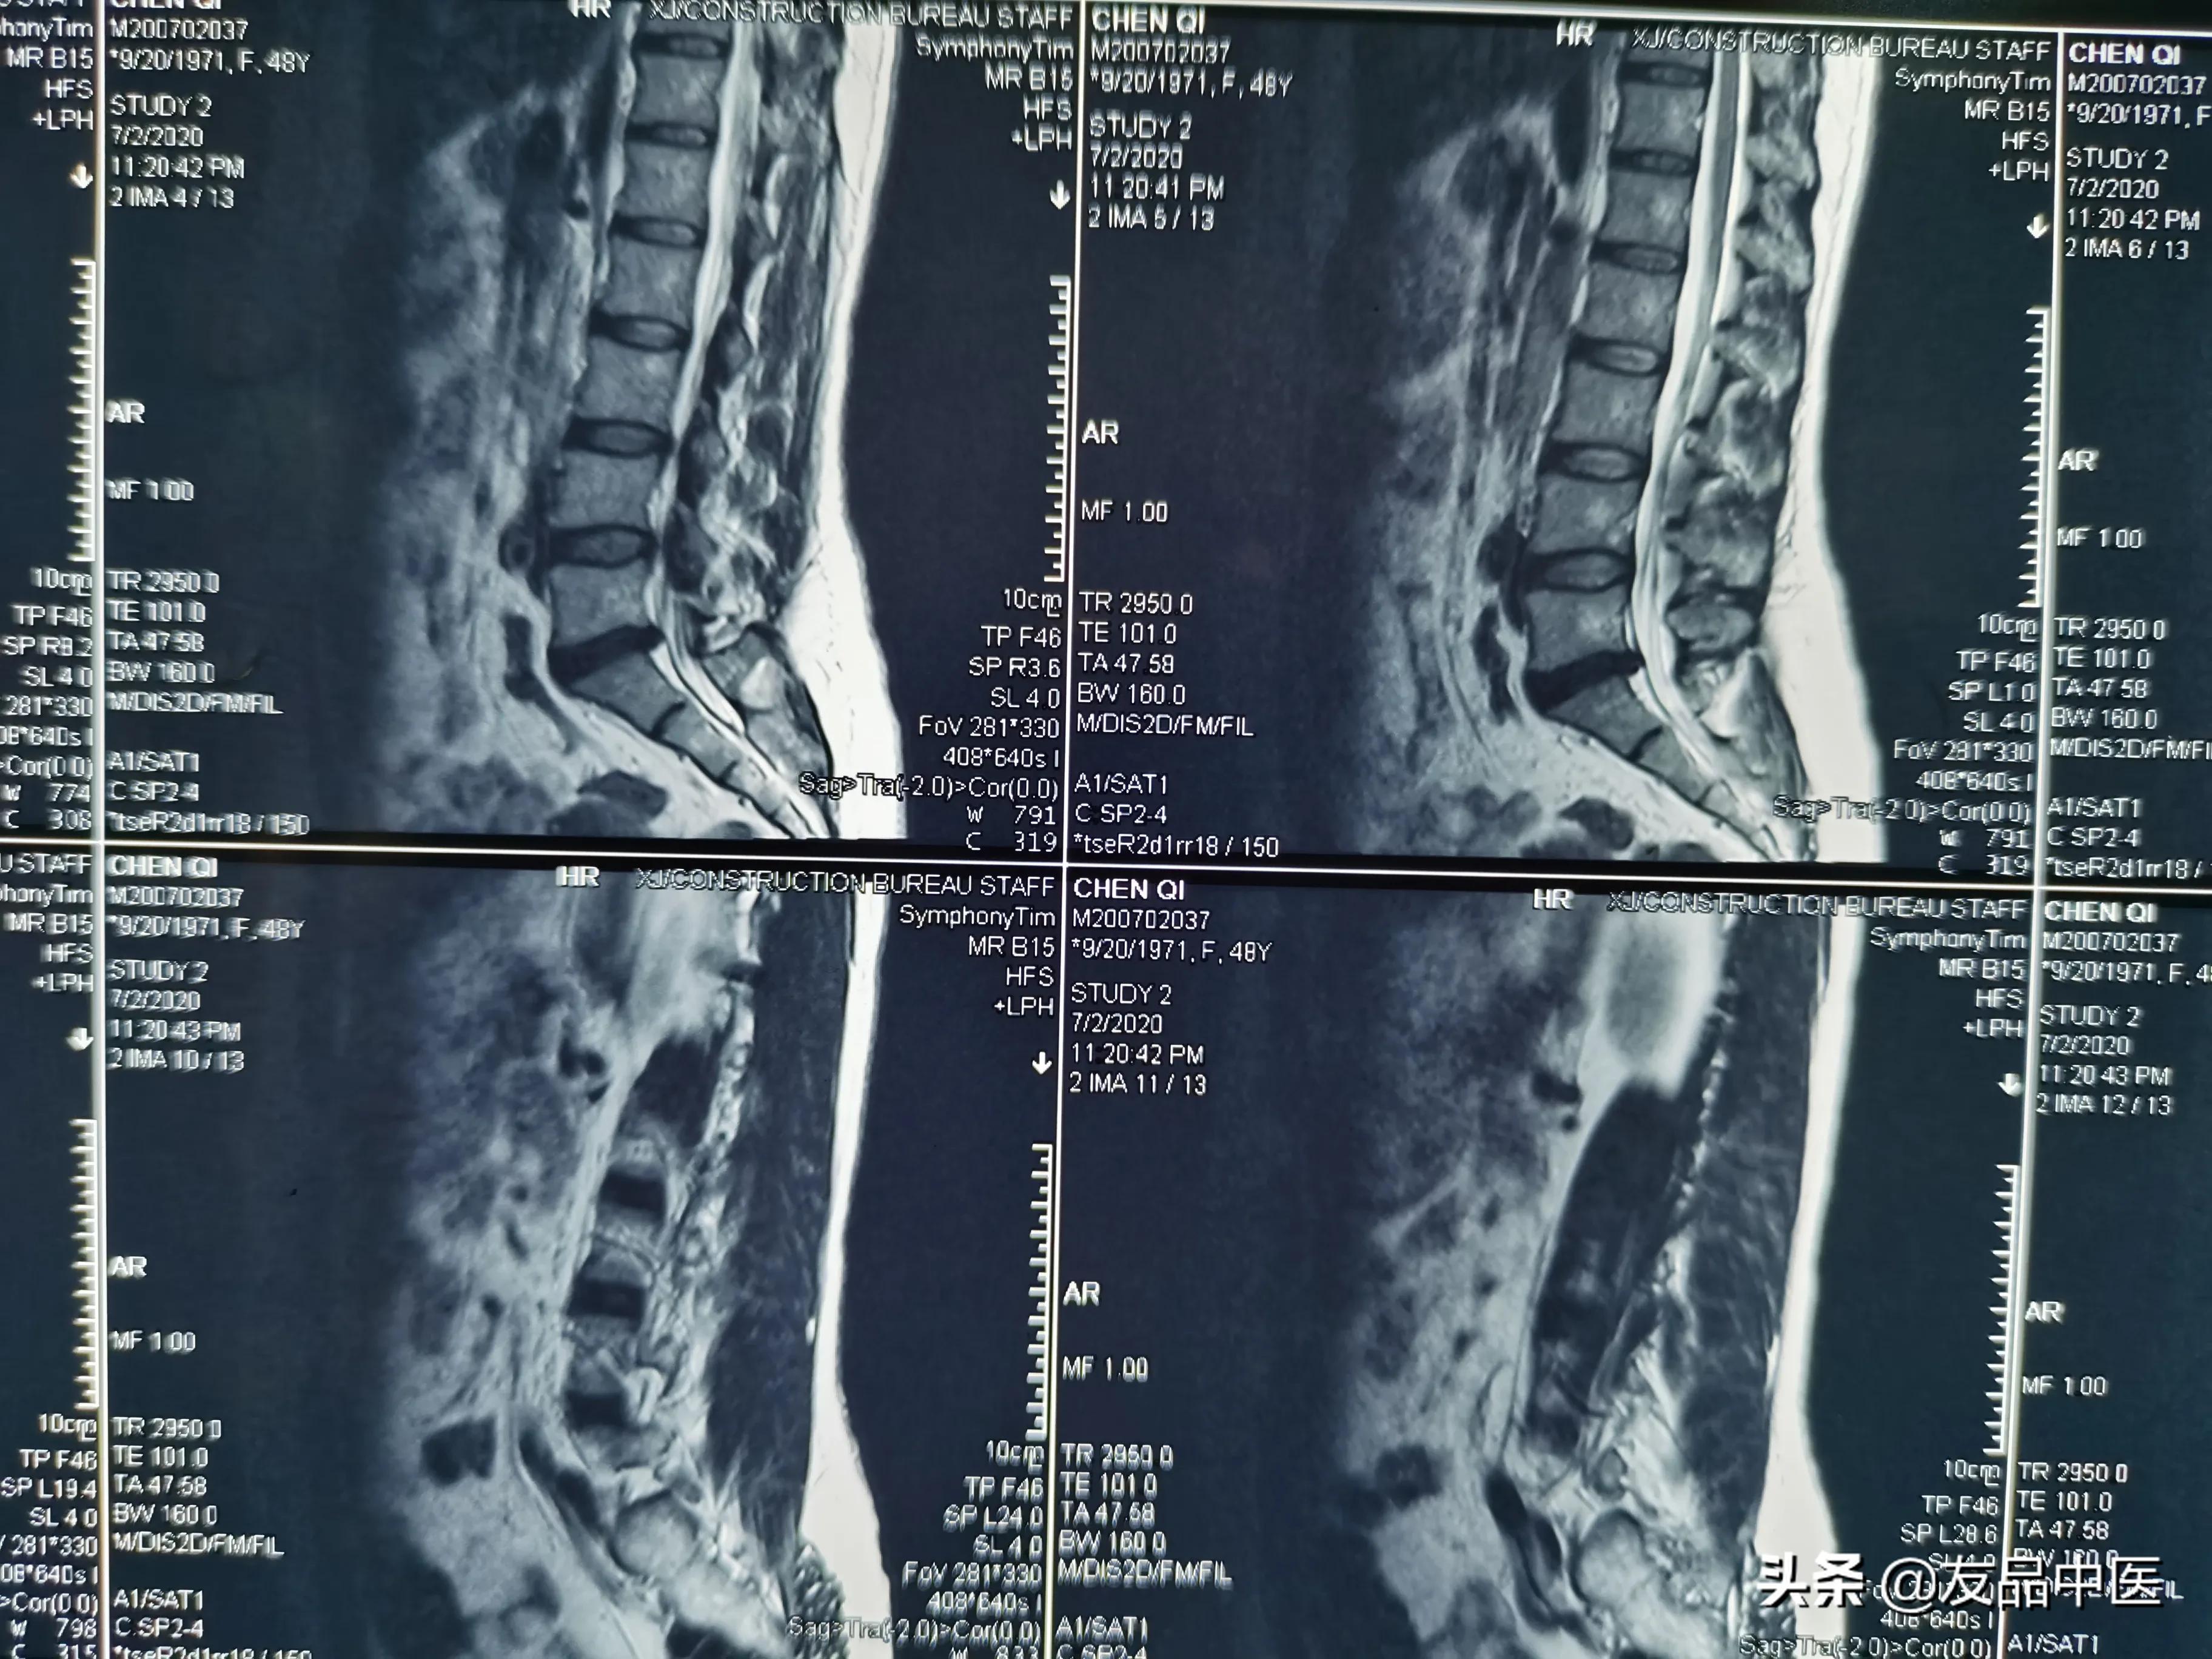

2、盘源性腰痛:这个疼痛特点是只是在腰周一带疼痛,没有放射性麻木,疼痛,偶尔也会引发腿部不适,但其疼痛不会超过膝关节,在腰椎中线,臀部,大腿外侧为多见。

还有些患者疼痛不明显,但在久坐久站后会出现下肢沉重,或双侧臀部有沉重感。休息后并不能马上缓解,早期推拿针灸缓解快,后期反弹间隔时间短#健康守护者##老当益壮##非常病例#

它的产生源头往往是椎体的退行性改变,或提示终板炎症。这样的疼痛看似不复杂,但理疗康复效果缓慢。